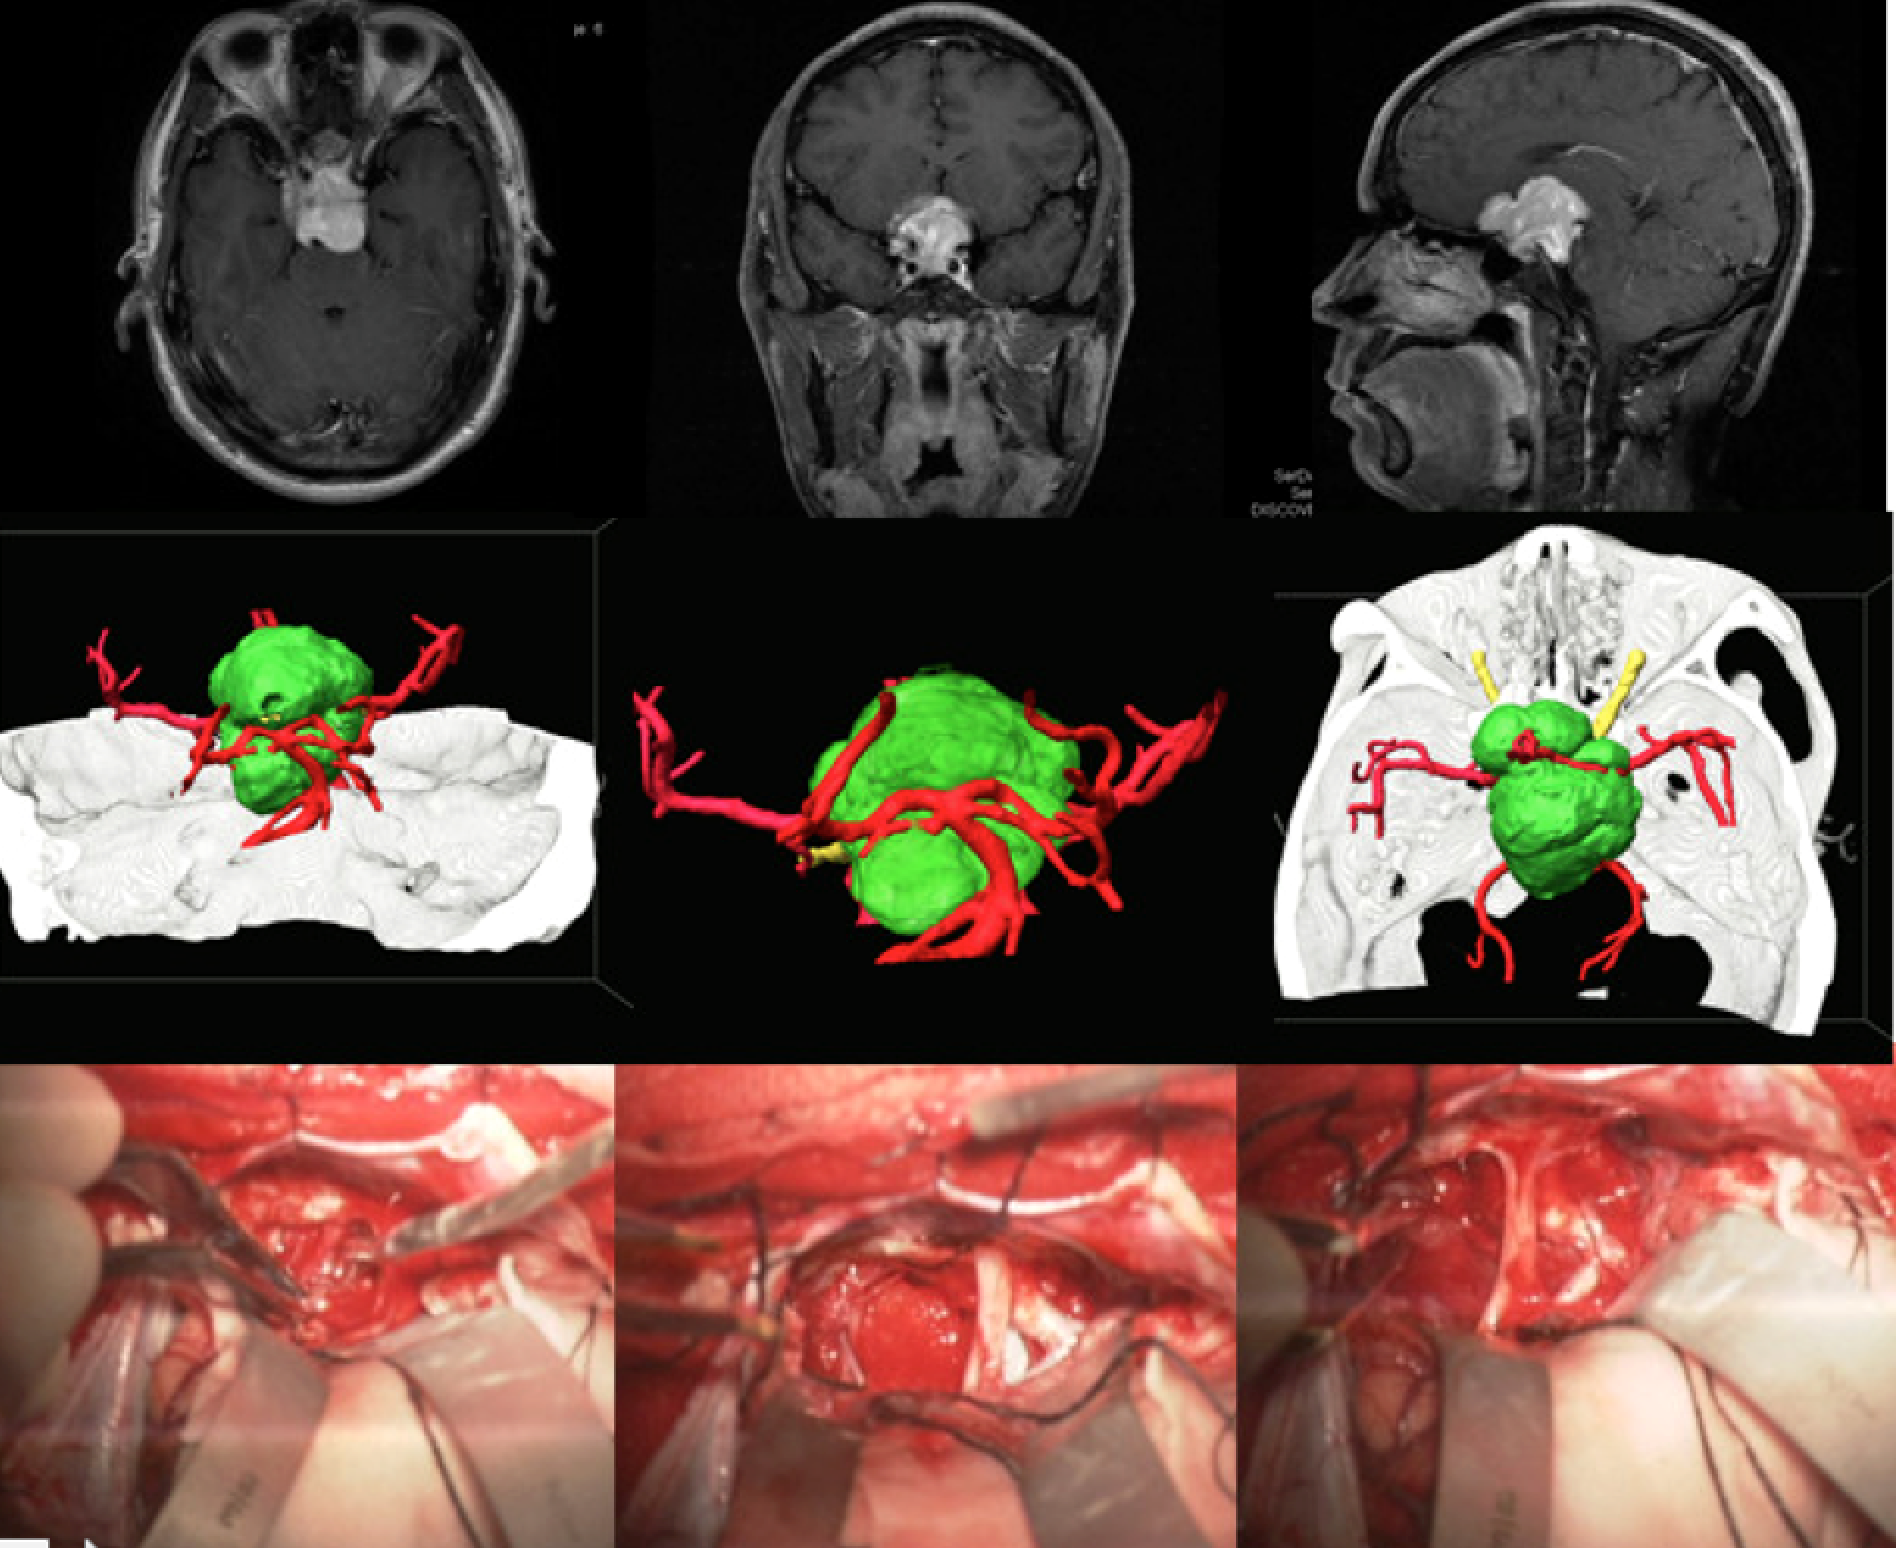

多模态影像融合及虚拟现实技术在颅底肿瘤中的应用

虚拟现实技术在颅底肿瘤中的应用